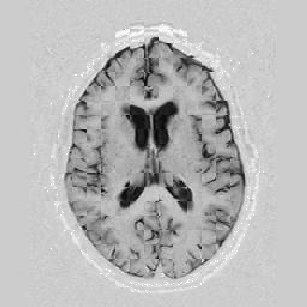

Another larger group of experiments enabled me to study the effects of multi-scale NRR. The results are shown in the form of chequerboard images in Figure [*]. In terms of resolution levels, higher numbers mean that the images are coarser.

Figure: Multi-scale NRR (increasing resolution). From left to right, top then bottom:before NRR; after 5 iterations of NRR at level 2 (higher is coarser); after another 5 iterations of NRR at level 1.